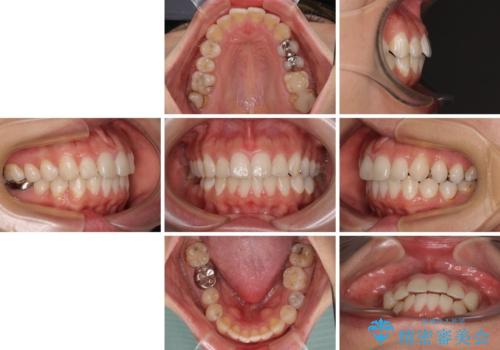

- 口元の突出感と奥歯のむし歯を気にして来院された患者様です。

奥歯の虫歯は事前に矯正治療用の仮歯に置き換えて矯正治療を行い、装置除去後にセラミッククラウンにて補綴治療を行うこととしました。

通常は上下左右の第一小臼歯4本を抜歯することになりますが、左側下顎の第二小臼歯は既に根管治療をされており、予後が良くないとのことでこの歯を抜歯し、ワイヤー装置にて矯正治療を行うこととしました。

第二小臼歯抜歯はイレギュラーな治療手段であり、治療期間が延びる傾向にありますが、予定よりも早い2年間で終えることができました。